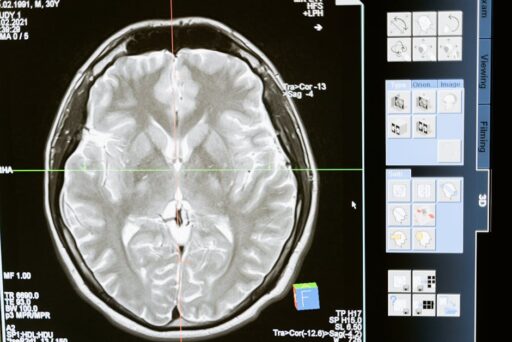

Traditional brain-computer interfaces often rely on implanted electrodes or scalp surface electrodes (EEG). Implanted electrode systems can yield high-fidelity signals but require surgery and carry infection, recovery, and long-term biocompatibility challenges. Noninvasive approaches typically trade signal fidelity for safety and accessibility.

Merge Labs claims its path will use molecular interfaces and deep-penetrating modalities such as ultrasound to transmit and receive information from neural tissue. If proven feasible at scale, those techniques could offer a middle ground: richer neural signals than standard EEG without the invasiveness of surgical implants.